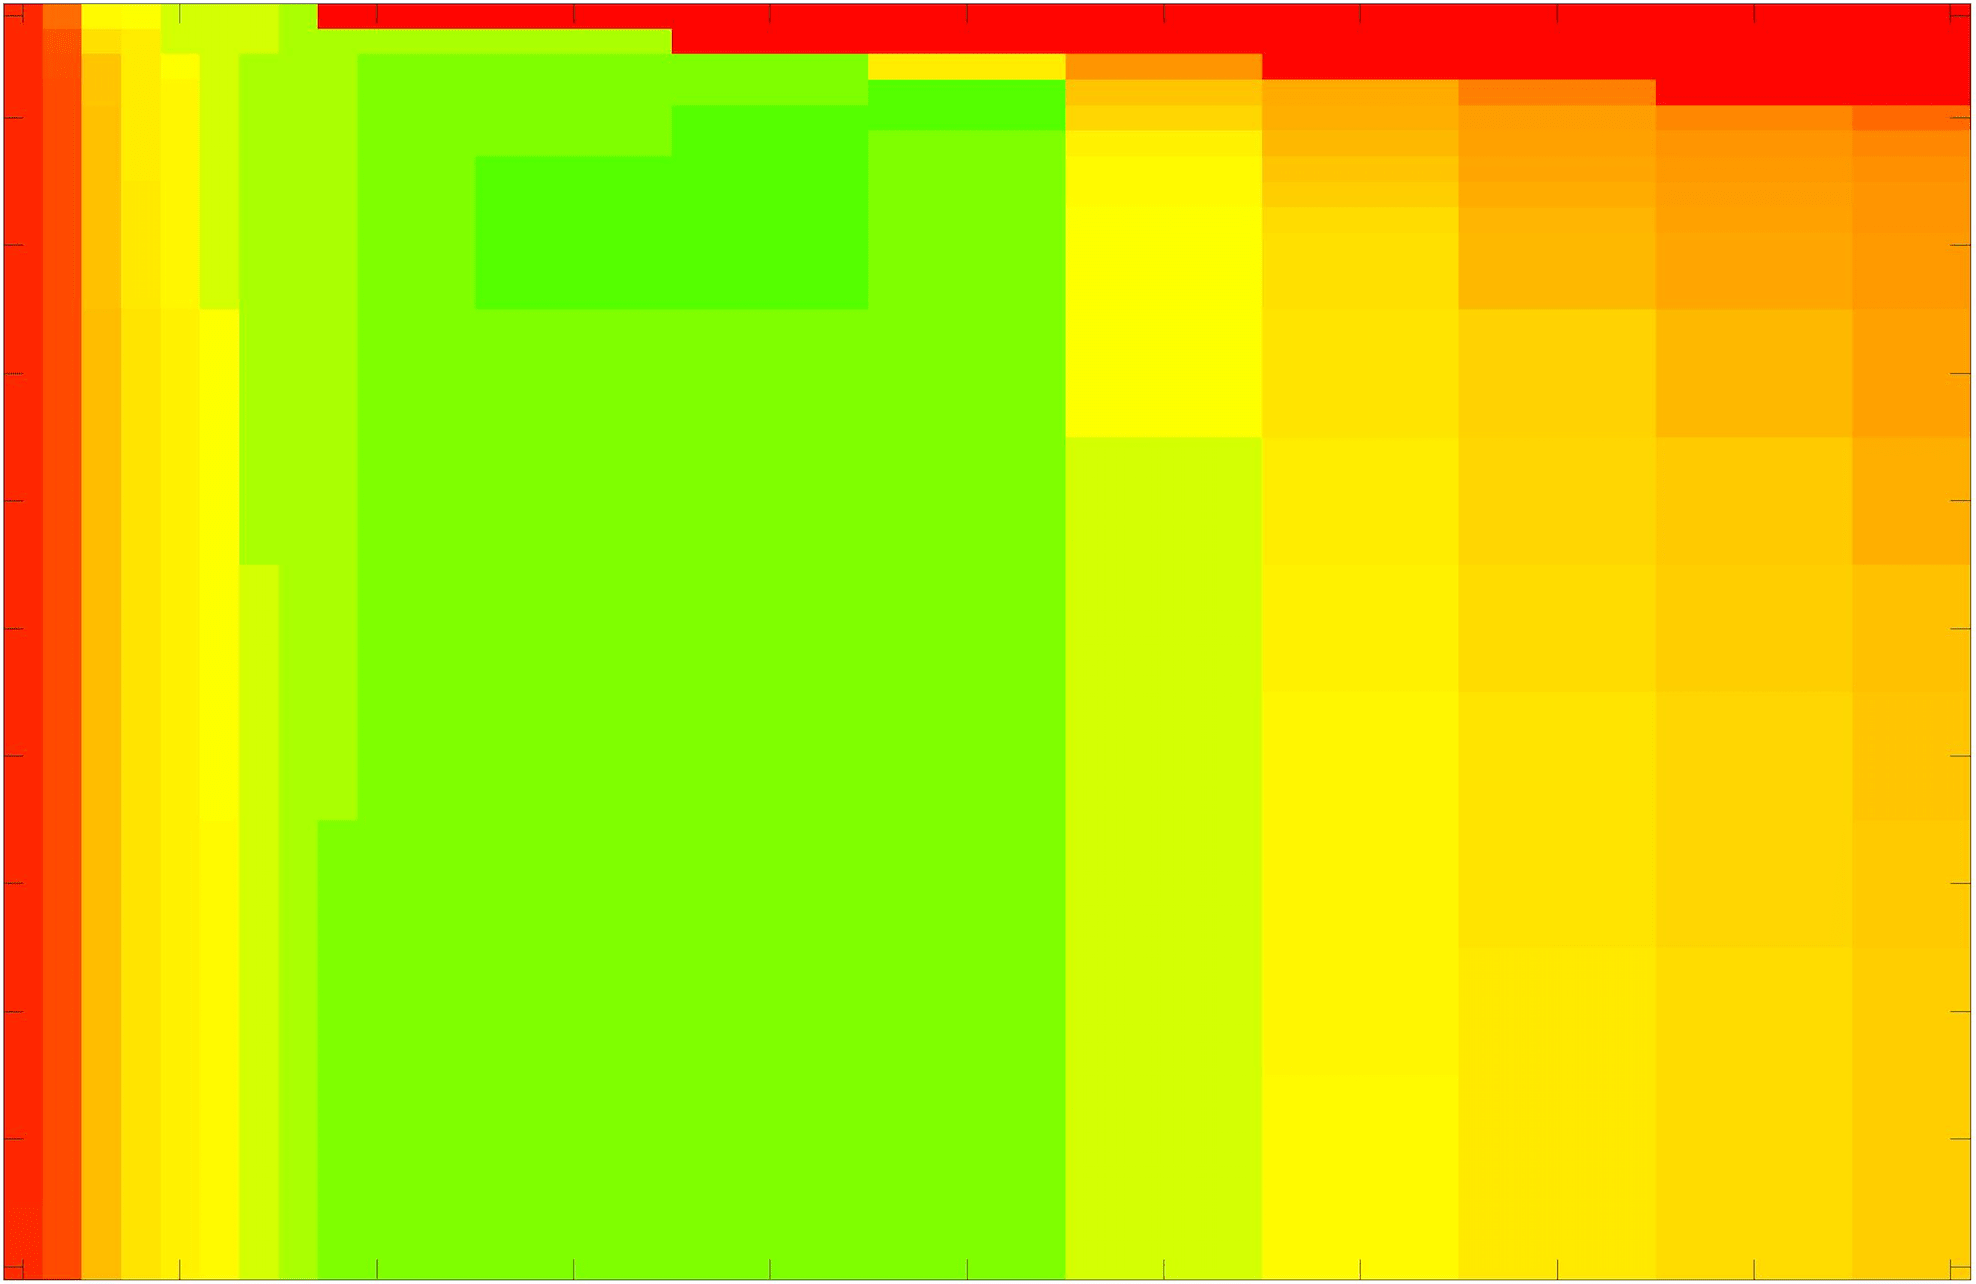

We define the proposed data fitting functional as follows:

for and as defined in (33). This is consistent with respect to the intensities of the observed object and the concept of selective segmentation. In Fig. 3 we see the difference between CV and the proposed fitting terms for given user input on a CT image. For the CT image, the CV fitting terms are near 0 within the target region. This is despite there being a distinct homogeneous area with good contrast on the boundary. This illustrates the problem we are aiming to overcome. With the proposed fitting term this phenomenon should be avoided in cases like this. By defining as in (33) there is no contradiction if the foreground and background intensities of the target region are similar.

where refers to the number of points in the enclosed region. This takes values in the range , with higher TC values indicating a more accurate segmentation. In the following we will represent accuracy visually from red () to green (), with the intermediate scaling of colours used shown in Fig. 8. This will be particularly relevant in §7.2.

The TC values for the parameter sets are presented as heatmaps in Figs. 11–13. A heatmap is a convenient way to display accuracy results for hundreds of tests concisely. In Fig. 9 we give an example heatmap with the same axes used for those in Figs. 11–13. For each of the combinations of parameter values we give the TC value of the segmentation result and represent it by the appropriate colour. The corresponding colour scale is shown in Fig. 8. Qualitatively, the more green areas of the heatmap the more accurate the model is for a wider set of parameters. Example results for Test Image 5 when varying (with ) for the proposed model are given in Fig. 10. Here it can be seen what each accuracy result corresponds to visually.

Note. The axes have been removed from the heatmaps in Figs. 11–13 for presentational clarity. However, to be explicit, the axes used in all heatmaps are the same as those in Fig. 9.

Synthetic Images. These results are presented in Fig. 11. For Test Images 1–2 we see poor parameter robustness from all competing models, except for GAV which performs reasonably well. However, the proposed model has minimal parameter sensitivity for these images, with good results achieved for almost every combination of values tested. For Test Image 3 all models have a reasonable parameter range (except for RSF), however the proposed model gives better quality results for a wider parameter range. The other models achieve reasonable results here as the foreground intensity of the ground truth is greater than the background , whereas for Test Images 1–2 they are equal . These results highlight the key advantage of the proposed model.

Real Images. In Fig 12 we present results for Test Images 4–6. Here, the proposed model performs in a similar way to its competitors because these images are more typical selective segmentation problems in the sense that there is a clear distinction between the foreground and background intensities. In particular, the values in each case are: Test Image 4 , Test Image 5 , and Test Image 6 . It can be seen that the proposed model is competitive compared to previous approaches. The performance is quite poor for Test Image 5, but is arguably still the best for this challenging case. In Fig. 13 we present results for Test Images 7–9. Here the proposed model outperforms previous approaches significantly for each image. This is mainly due to the type of image considered. Specifically, the true intensities are: Test Image 7 , Test Image 8 , and Test Image 9 . The proposed model is capable of achieving results where , with other models failing completely in these cases.